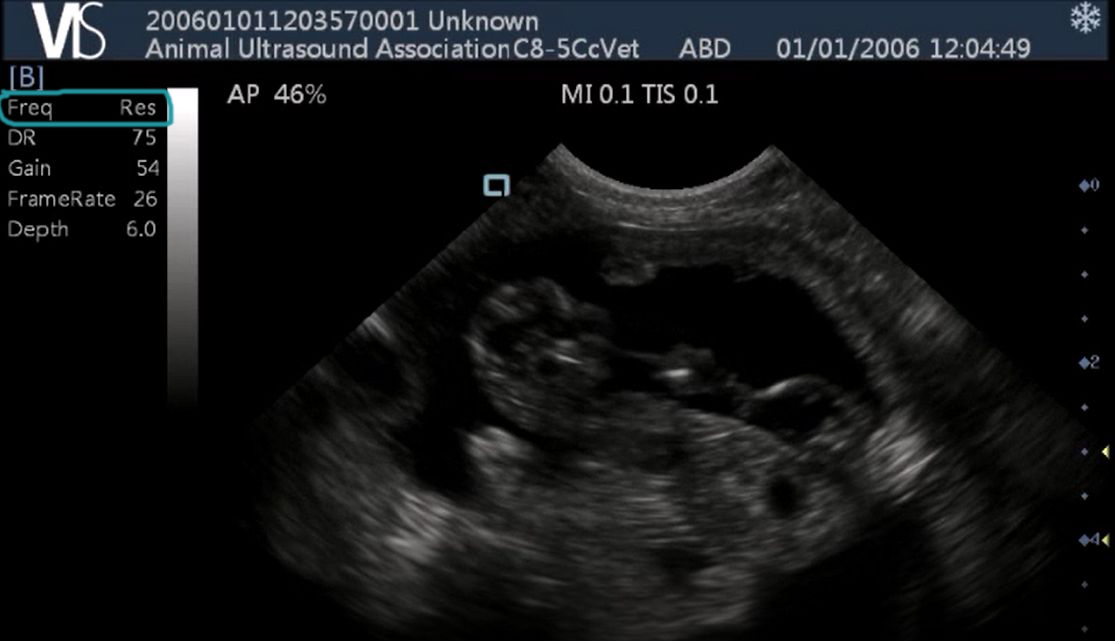

Below are some examples of scan images taken at higher frequencies. The scanning frequency has been circled in blue. The below images are captured at high resolution.

High resolution Scan Pad image

High resolution Scan Pad canine scan